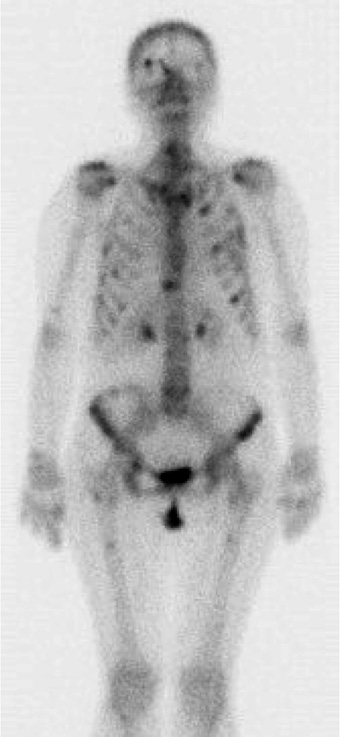

При дополнительном обследовании (позитронно-эмиссионная томография, совмещенная с компьютерной томографией – ПЭТ-КТ всего тела 09.2015; рис. 3) выявлены множественные метастазы в печени, селезенке, лимфоузлах средостения и брюшной полости, желудке, костях.

Рис. 3. ПЭТ-КТ всего тела от 09.2015.